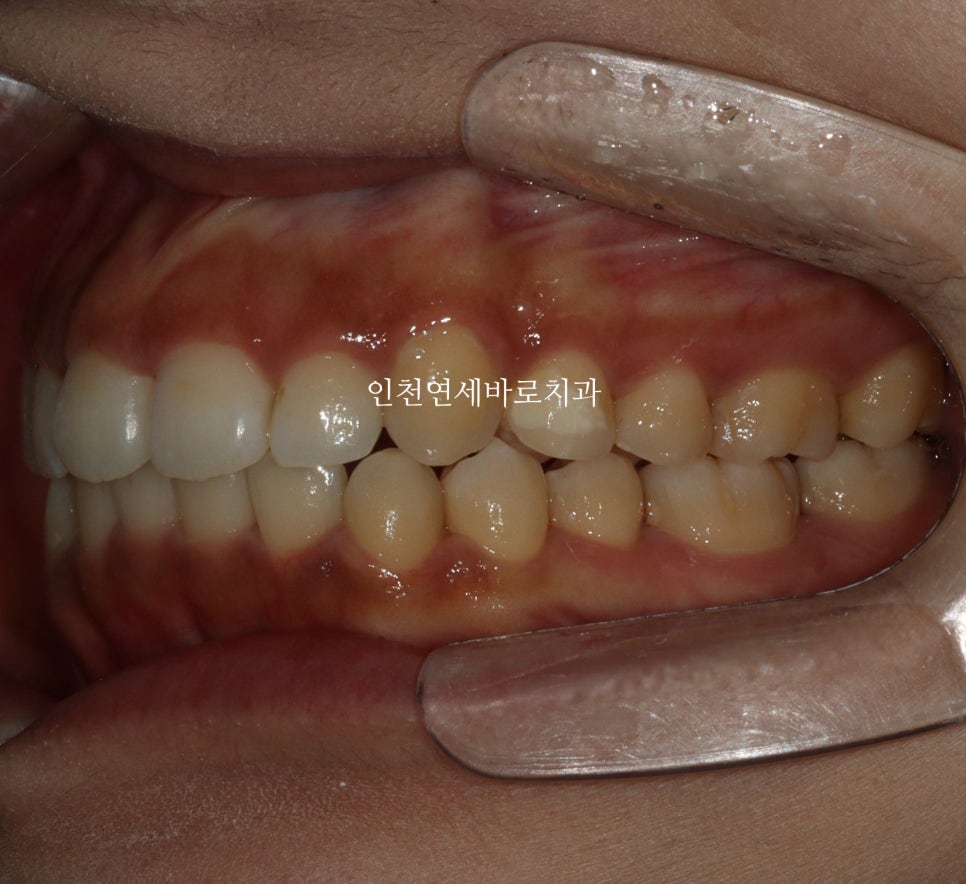

전후 비교입니다

전 후 교합의 비교입니다.

안정적으로 교합이 형성되었습니다

교정 끝난 직후의 사진이라 아주 약간은 제 마음에 안드는 부분이 있지만